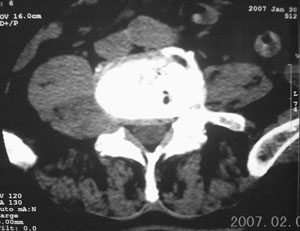

男,75岁,腰周疼5-6年。别无症状。

右侧椎旁、侧隐窝软组织肿块,呈不规则双极征改变,椎体后外缘骨质弧形压迹,椎间孔扩大;考虑神经源性肿瘤,神经鞘瘤可能性大,需与神经纤维瘤相鉴别。

病变侧椎间孔扩大,椎体缘受压吸收;

考虑神经源性肿瘤,神经鞘瘤可能;